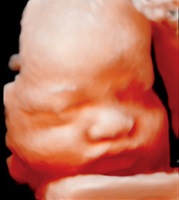

5d ultrahang

(magzati ultrahang, magzati Doppler-áramlásvizsgálatok (flowmetria), diagnosztikus kismedencei ultrahang, petefészkek, a méhtest és endometriózis ultrahang vizsgálata)A Medconnexus Gyógyászati Központban a világszínvonalú ''SAMSUNG WS80 ELITE” és „MEDISON'' valamint ''TOSHIBA'' ultrahangkészülékek állnak rendelkezésre. Lehetőség van a legmodernebb „5 Dimenziós” ábrázolásmódra, hüvelyi, hasi vizsgálatokra, doppler-áramlásmérésre, DVD-felvételek készítésére, valamint fénykép készítésére.

A terhesgondozás elengedhetetlen elemeként a terhesség igazolásától az egész terhesgondozás során nyomon követjük a magzat és a méhlepény méhen belüli fejlődését, elhelyezkedését. A vizsgálati protokolloknak megfelelő időpontokban elvégezzük a szükséges paraméterek mérését, mint például a tarkótáji bőrredő, az orrcsont, vagy a magzati vesék mérését. A magzati fejlődés és állapot diagnosztikájának részeként flowmetriás (áramlás-diagnosztikai) vizsgálatokat végzünk. Az 5 dimenziós felvételekkel családi eseménnyé emeljük a várandósok gondozását.